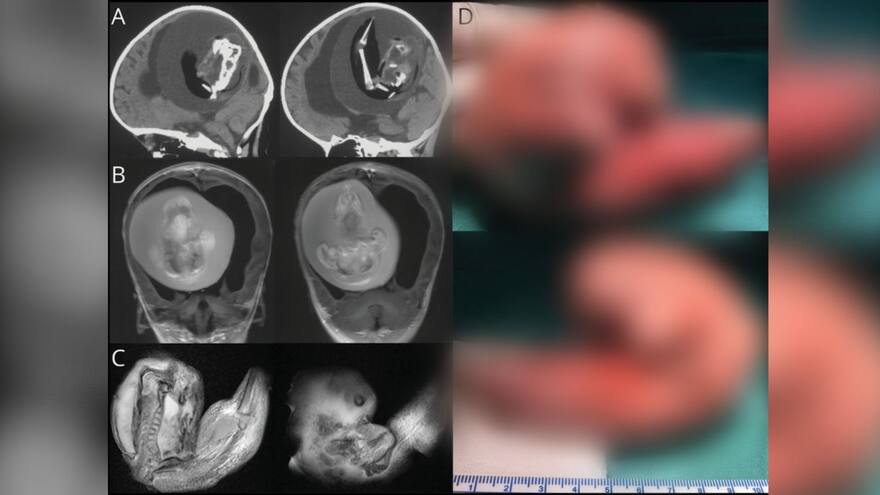

Feto en la cabeza